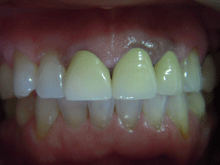

オールセラミックス

金属を使わずに全てセラミックを使用し、光の透過性を上げる事により自然な白い歯に回復させる方法です。

現在では土台から白い材質(ファイバーポストなど)の物を使用することにより、さらに透明感が増し天然歯に近似しています。

オールセラミックは近年進化を遂げており、強度や接着性がかなり改善され、審美的にとても優れたものと成って来ております。

オールセラミックにも色んな種類がありますが、当院ではe-max(二ケイ酸リチウムガラスセラミック、)ジルコニアセラミックスを採用しています。

症 例